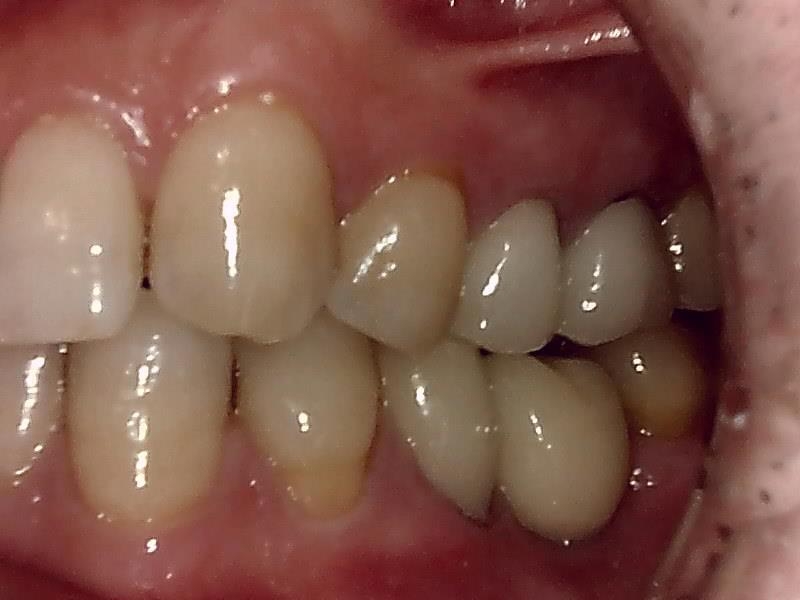

左側面観